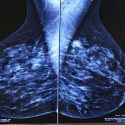

Μαστογραφία

Μαστογραφία

Μαστογραφία και τομοσύνθεση